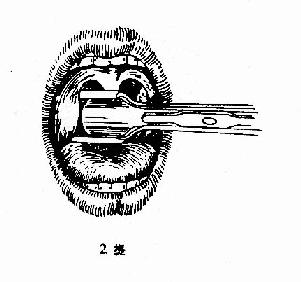

(二)挤切法(guillotine method)(图6-3):

2.操作:病人取仰卧或坐位,助手将其头部固定,置入开口器后,手术者以压舌板压舌,暴露扁桃体下极,右手持挤切刀,从扁桃体下极套入,再转动刀环,使其位于扁桃体和咽腭弓之间,将扁桃体后面及上极套入,并向舌腭弓方向提起,这时扁桃体在舌腭弓下隆起成一“包块”,即用左手拇指或食指将“包块”挤压入环内,随即收紧刀柄,推动刀杆前进,使刀片切入刀环的尽端,以迅速有力的扭转及提拔动作切下扁桃体。以同法切除对侧扁桃体。助手迅速将患者头部侧转,使其将血吐出。止血方法同剥离法。

图6-3 扁桃体挤切术